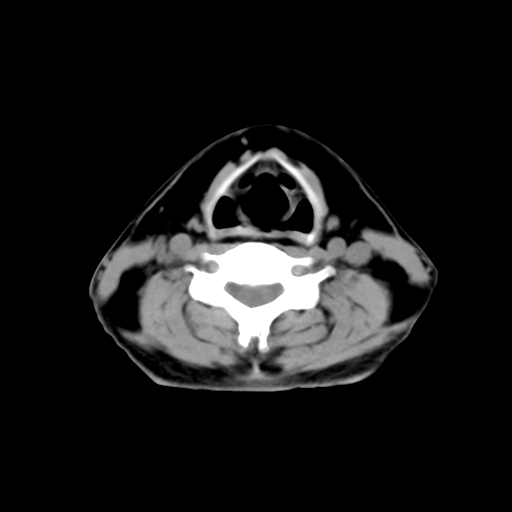

标题: CT24019:男,45岁,发现颈部肿物5个月。 [打印本页]

男,45岁,发现颈部肿物5个月,彩超示:双侧颈部及下颌部软组织增厚。

考虑双侧颈项部良性对称性脂肪增多症。